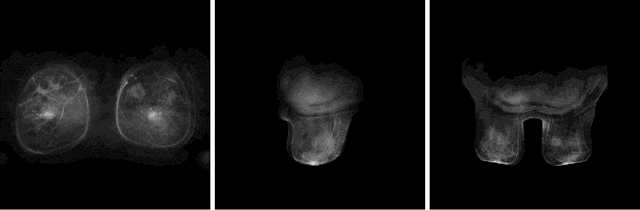

Abstract:Objective: To develop an automatic image normalization algorithm for intensity correction of images from breast dynamic contrast-enhanced magnetic resonance imaging (DCE-MRI) acquired by different MRI scanners with various imaging parameters, using only image information. Methods: DCE-MR images of 460 subjects with breast cancer acquired by different scanners were used in this study. Each subject had one T1-weighted pre-contrast image and three T1-weighted post-contrast images available. Our normalization algorithm operated under the assumption that the same type of tissue in different patients should be represented by the same voxel value. We used four tissue/material types as the anchors for the normalization: 1) air, 2) fat tissue, 3) dense tissue, and 4) heart. The algorithm proceeded in the following two steps: First, a state-of-the-art deep learning-based algorithm was applied to perform tissue segmentation accurately and efficiently. Then, based on the segmentation results, a subject-specific piecewise linear mapping function was applied between the anchor points to normalize the same type of tissue in different patients into the same intensity ranges. We evaluated the algorithm with 300 subjects used for training and the rest used for testing. Results: The application of our algorithm to images with different scanning parameters resulted in highly improved consistency in pixel values and extracted radiomics features. Conclusion: The proposed image normalization strategy based on tissue segmentation can perform intensity correction fully automatically, without the knowledge of the scanner parameters. Significance: We have thoroughly tested our algorithm and showed that it successfully normalizes the intensity of DCE-MR images. We made our software publicly available for others to apply in their analyses.